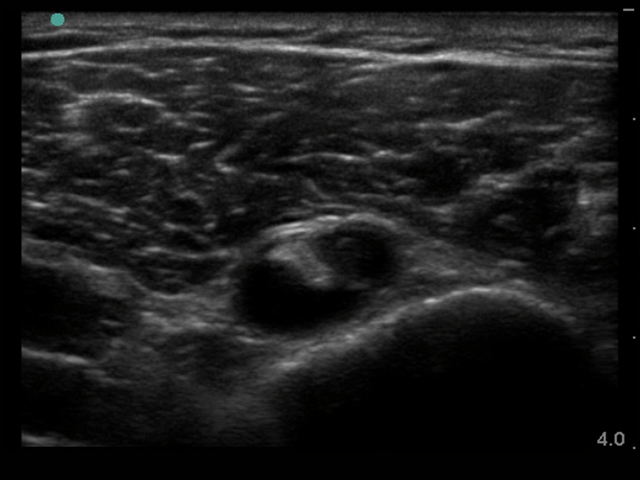

Image - Épaule : Épanchement du biceps et mésotendon